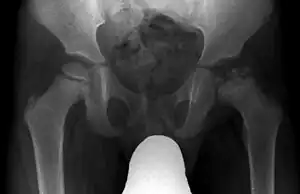

Radiograph of a person with Legg–Calvé–Perthes disease

X-rays of the hip may suggest and/or verify the diagnosis. X-rays usually demonstrate a flattened, and later fragmented, femoral head. A bone scan or MRI may be useful in making the diagnosis in those cases where X-rays are inconclusive. Usually, plain radiographic changes are delayed six weeks or more from clinical onset, so bone scintigraphy and MRI are done for early diagnosis. MRI results are more accurate, i.e. 97–99% against 88–93% in plain radiography. If MRI or bone scans are necessary, a positive diagnosis relies upon patchy areas of vascularity to the capital femoral epiphysis (the developing femoral head).[11]